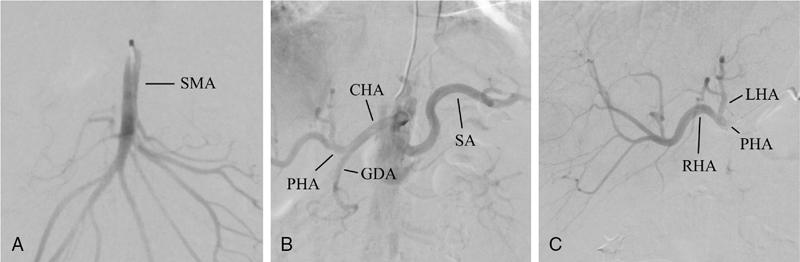

Technique

Celiac axis

SMA

Hepatic